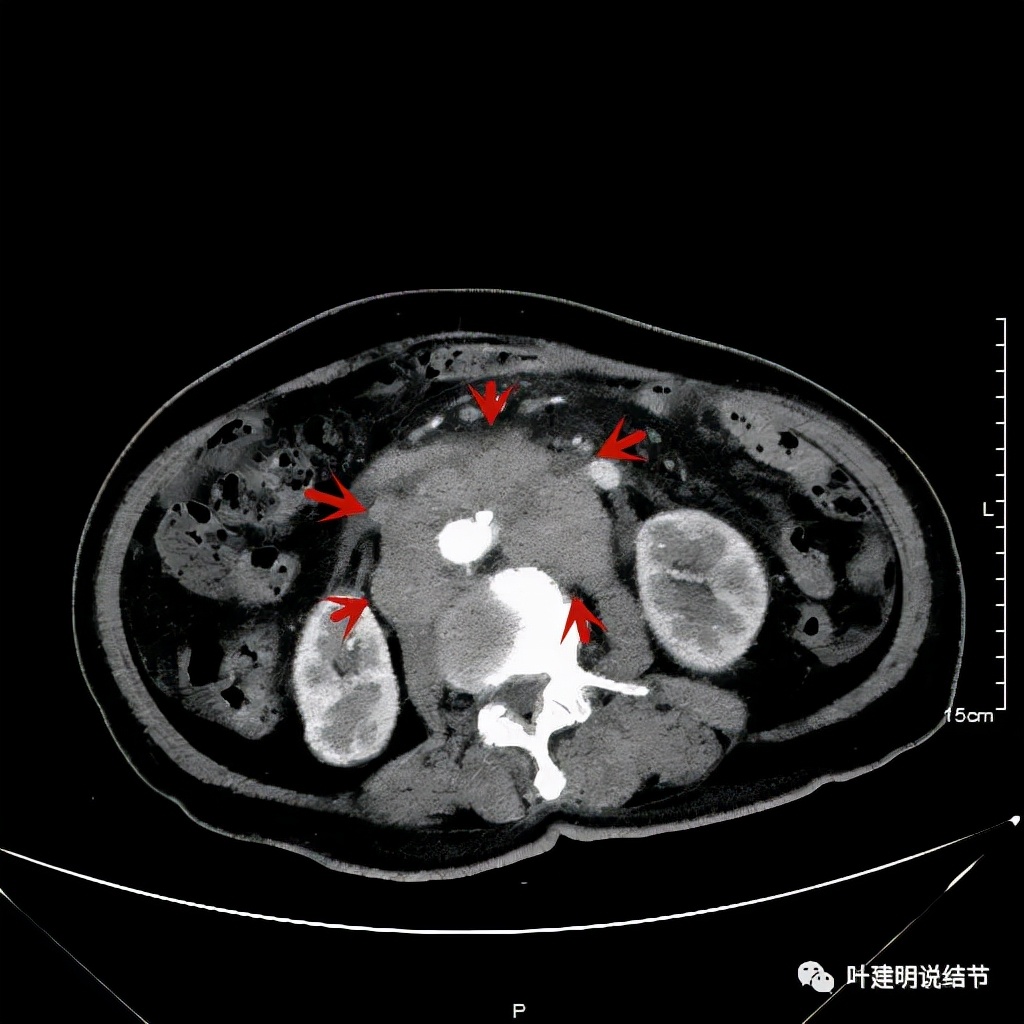

其实胸部CT示食管的病变感觉并不厉害,外侵或纵隔内转移均不明显,但其腹部的CT让人大吃一惊!

上图是初发现时的CT影像报告,其他CT图像上红色箭头所指范围内都是肿瘤,整合成团,挤压血管以及正常器官结构。你有见过原发灶这么不显眼,而腹部转移灶这么厉害的食管癌吗?但经过穿刺证实是转移性鳞癌,结合病史考虑是食管癌转移。手术自然是不可能了根治了,放疗也不合适,经过MDT并与患方充分沟通,依据食管癌治疗指南: